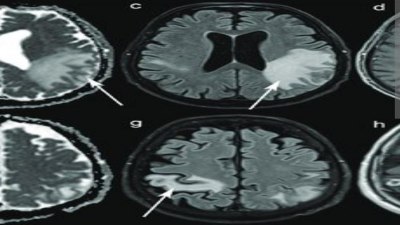

एमआरआई कराने पर हो रहा स्पष्ट

विशेषक्ष चिकित्सकों के मुताबिक भूल जाने की बीमारी वाले गंभीर मरीजों को लेकर आने पर, उन मरीजों का एमआरआई करवाया जाता है। एमआरआई की रिपोर्ट देखने से स्पष्ट होता है, कि 25 साल के युवक के दिमांग की नसें उस तरह से सूख गई है, जैसे 75 से 80 साल के उम्र के बुजुर्ग की सूख जाती है। इसी तरह से मोबाइल, एलईडी और नशा अधिक करने वाले मरीजों का याददाश्त के साथ-साथ जीवन बचाना मुश्किल हो जाता है।

side effect of mobile Death राजनांदगांव से एक 45 साल के व्यक्ति को भूल जाने की शिकायत लेकर परिवार के लोग दुर्ग पहुंचे। वह खाना खाने के बाद भूल जाता था कि खाना खाया है। यहां चिकित्सकों ने जांच किया। मरीज मोबाइल अधिक वक्त तक उपयोग करता था। नशा भी करता था। मरीज की गंभीर स्थिति को देखते हुए एमआरआई करवाया गया। उसकी रिपोर्ट में नजर आया कि ब्रेन का केमिकल कम हो गया था। 80 साल के बुजुर्ग के दिमांग की नस जितना सूख जाती है, उतनी उसकी सूख चुकी थी। उस मरीज की जल्द ही मौत हो गई।

दुर्ग में रहने वाले एक 25 साल के युवक को चिकित्सक के पास लेकर आया गया। उसे पैरालिसिस अटेक हुआ है। परिवार के सदस्यों ने बताया कि यह युवक 20 साल के उम्र से शेयर ट्रेडिंग का काम कर रहा था। मोबाइल और एलईडी के सामने उसका घंटों बीत जाता था। अचानक उसके सीधे तरफ के हिस्से में पैरालिसिस अटेक आया है। युवक का 18 माह पहले ही विवाह हुआ है। मरीज का एमआरआई करने पर स्पष्ट हुआ है, कि जरूरत से अधिक इस्तेमाल करने से दिमांग की नसें सूख गई हैं।